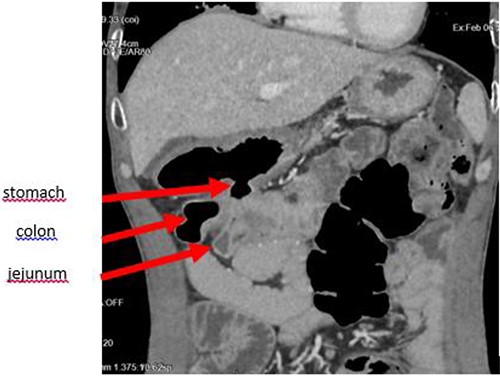

The enteroscan showed a large fistula between the anterior face of the stomach, the jejunum and the transverse colon (Figs 2 and 3). The diagnosis of GJF was then established. The patient underwent surgery. A revision gastrectomy, truncal vagotomy and segmental resection of the jejunum and transverse colon with Roux-en-Y reconstruction were performed. During the follow-up, the patient remained well and gained weight.

Coronal section showing the parietal defect of the greater curvature of the stomach communicating with the colon.